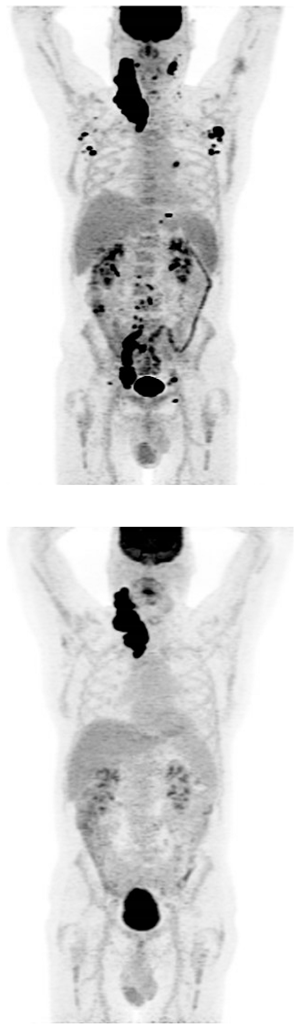

R-GDP: cycle 1 received

PET confirmed progression

Plan for CAR-T cell therapy

Time from CAR-T cell therapy consultation to leukapheresis was 4 days

No holding therapy administered, but bridging therapy with Pola-R considered

Unfortunately, T-cell collection was insufficient to enable an adequate CAR-T cell product

Potential candidate for BsAbs